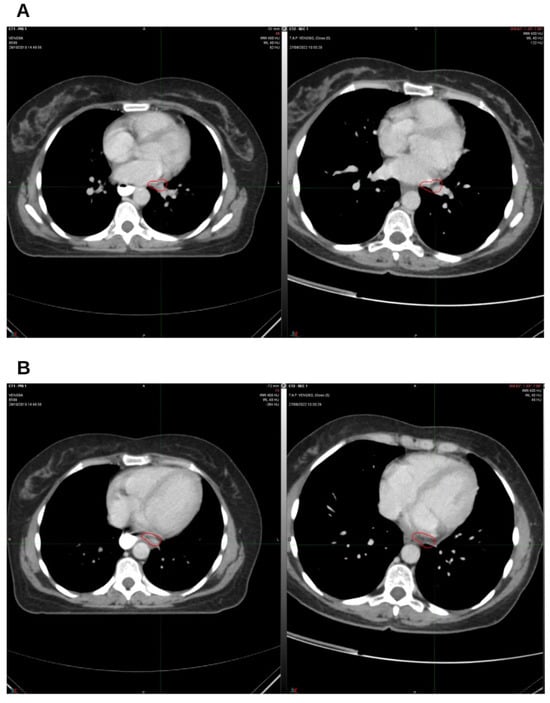

Integrative Use of Cannabidiol, Melatonin, and Oxygen–Ozone Therapy in Triple-Negative Breast Cancer with Lung and Mediastinal Metastases. A Case Report

Background and Clinical Significance: Breast cancer is the most frequent malignancy in women. Metastatic breast cancer is considered a treatable but incurable condition, with a median overall survival of only 2–3 years. Among its subtypes, triple-negative breast cancer (TNBC) accounts for a high proportion of breast cancer-related deaths. It is characterized by an aggressive clinical course, early recurrence, and a strong propensity for visceral and brain metastases. Case Presentation: We report the case of a Caucasian woman who developed systemic disease recurrence with lung and mediastinal lymph node metastases, occurring two years after her primary diagnosis and treatment for TNBC. The patient received three months of chemotherapy combined with an adjuvant integrative protocol consisting of melatonin, cannabidiol, and oxygen–ozone therapy. This combined approach led to the complete disappearance of the lung nodules. Subsequently, stereotactic radiotherapy was performed and, in association with the ongoing integrative treatment, resulted in a significant reduction in mediastinal adenopathy. Introduction of immunotherapy, supported continuously by the same adjuvant strategy, achieved a complete and durable remission. Strikingly, the patient remained disease-free five years after the diagnosis of lung and mediastinal metastases. Conclusions: This clinical case highlights the potential benefit of using melatonin, cannabidiol, and oxygen–ozone therapy as part of an integrative approach in patients with aggressive metastatic TNBC. While it is not possible to establish causality from a single case, the sustained remission observed suggests that such unconventional adjuvant strategies could play a supportive role in enhancing the efficacy of standard oncologic therapies. Full article

Figure 1